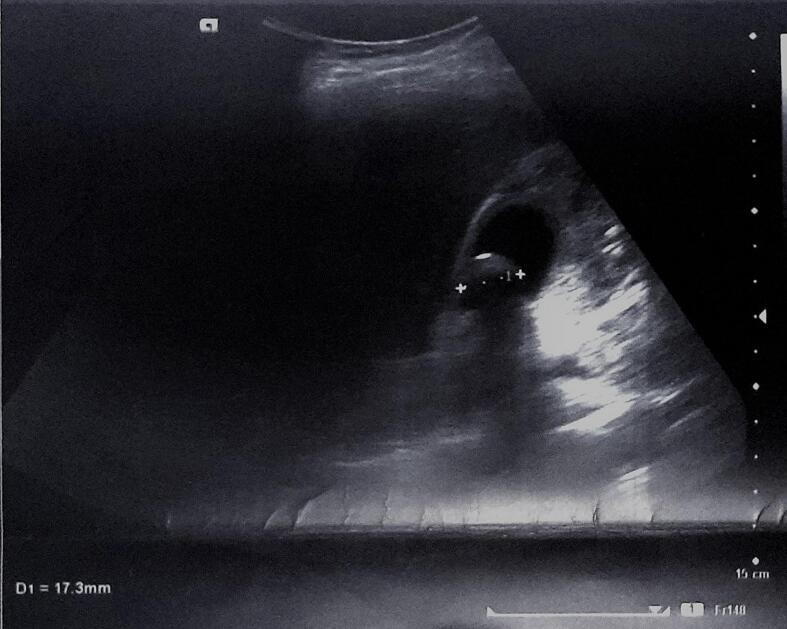

We described two cases in which a woman aged 27 years and a man aged 30 years presented with acute and chronic cholecystitis symptoms, respectively. The ultrasound revealed calculous cholecystitis. The cholecystectomy was performed, and the pathological examination of the surgical specimen revealed eosinophilic cholecystitis.

我们描述了两例病例,分别为一名27岁女性和一名30岁男性,前者表现为急性胆囊炎症状,后者表现为慢性胆囊炎症状。超声检查显示为结石性胆囊炎。实施了胆囊切除术,手术标本的病理检查显示为嗜酸性粒细胞性胆囊炎。